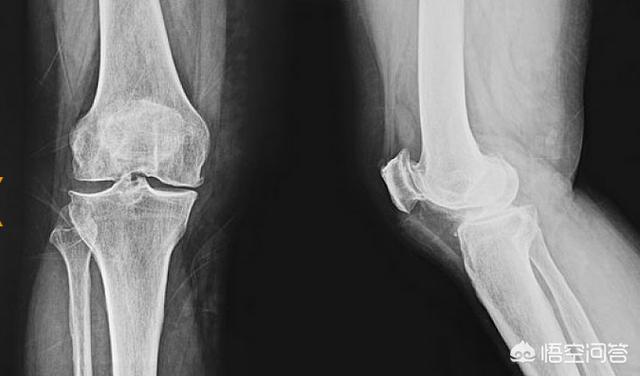

(1) Ältere Menschen über 50 Jahre leiden unter Verschleiß des Knorpels im Knie aufgrund der Degeneration der Gelenkfunktion, die Schmerzen in der medialen Seite des Knies hervorruft. Ältere Menschen körperlichen Rückgang, die Brüchigkeit des Gewebes um das Knie erhöht, zu Fuß in den Prozess der wiederholten Wechsel zwischen den beiden Beinen, die Knie mediale Wand immer wieder ziehen, mehr als die Grenze, dann gibt es einen leichten Riss Verletzungen und Ödeme um die Verletzung. Nach jahrelangem Zertrümmern ist der Knorpel der Gelenkfläche und der Meniskus erschöpft, so dass es zu einer Zertrümmerung zwischen dem medialen Femurkondylus und dem medialen Tibiakondylus kommt.

2) Bei jungen Menschen werden mediale Knieschmerzen in der Regel durch Schäden an den Kniebändern verursacht. Bei jungen Menschen sind die Schäden aufgrund der Dämpfung durch den sehr dicken Knorpel auf der Gelenkfläche und den Meniskusknorpel nicht sehr groß. Klinisch äußert sich dies durch Schmerzen und Schwellungen an der Innenseite des Knies. Trotz der Schmerzen sind im Röntgenbild keine knöchernen Veränderungen zu erkennen.

3, gibt es auch eine Art von inneren Knieschmerzen durch die Knie-Meniskus-Verletzung verursacht wird. Der Kniescheibenmeniskus ist eine Art Knorpel, der sich in der Mitte des Oberschenkels und der Wade des Kniegelenks befindet und eine wichtige Rolle bei der Übertragung der Kraft des Kniegelenks spielt. Wenn der Kniescheibenmeniskus beschädigt ist, kann die Kraft des Körpers nicht mehr gleichmäßig über das Kniegelenk übertragen werden, was eine vorzeitige Arthrose des Kniegelenks begünstigt, die dann zu Kniegelenkschmerzen führt. Eine Meniskusverletzung im Knie tritt am häufigsten in zwei Fällen auf: erstens bei einer traumatischen Verletzung. Sportarten sind anfällig für Kniemeniskusverletzungen. Zweitens: degenerative Verletzungen. Mit zunehmendem Alter degeneriert der Meniskus, reißt und wird beschädigt. Meniskusverletzungen treten oft gleichzeitig mit Kniebandverletzungen auf.

Die beiden häufigsten Symptome einer Kniemeniskusverletzung sind: Schmerzen und Schwellung an der Verletzungsstelle. Wenn die Innenseite des Knies schmerzt und anschwillt, liegt wahrscheinlich eine Verletzung des Innenmeniskus im Knie vor. Ein knackendes Geräusch im Kniegelenk und manchmal ein Gefühl, dass das Knie klemmt, sind häufig nach einer Innenmeniskusverletzung zu hören.